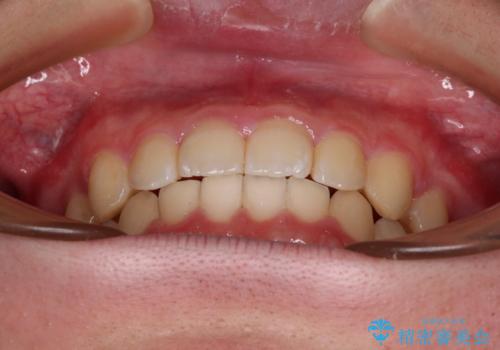

【モニター】斜めに突き出した前歯をインビザラインで改善

- 前方に傾斜した前歯を気にして来院された患者様です。

強く食いしばってしまう癖があり、下顎前歯に押し出されて上顎前歯が前方へ斜めに突き出している状態でした。

IPR(歯と歯の間を削る)を多用して、インビザラインにて矯正治療を行うこととしました。

口元を引っ込めるためのゴムかけを頑張っていただき、満足のいく上顎前歯の傾斜へ改善することができました。